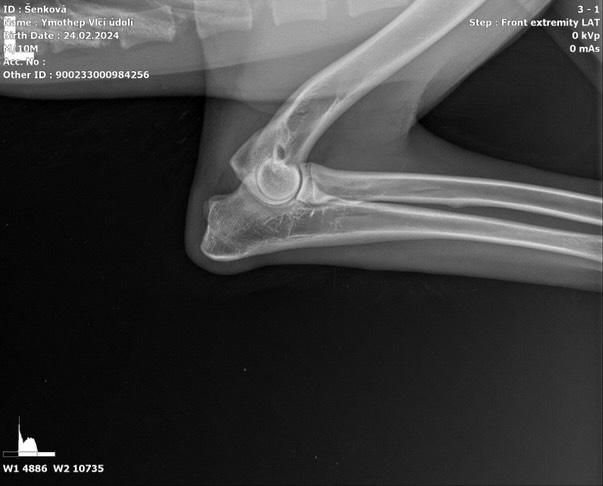

Ymhotep Vlčí Údolí

DOB: 02/24/24